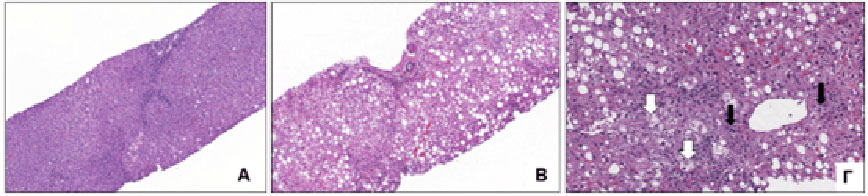

Ειδικοί μη επεμβατικοί δείκτες μπορούν με ασφάλεια να αναδείξουν ποιοι ασθενείς έχουν προχωρημένη βλάβη με ανάπτυξη ίνωσης ή ακόμα και κίρρωση και να παραπεμφθούν σε ειδικά κέντρα. Όμως, η διάγνωση της ΜΑΣΗ, δηλαδή της εξελικτικής μορφής της ΜΑΛΝΗ, βασίζεται ακόμη στη βιοψία ήπατος (Εικόνα 1), η οποία ενδείκνυται σε επιλεγμένους ασθενείς που παρουσιάζουν ασαφή αποτελέσματα στις τιμές μη επεμβατικών δεικτών καθώς και σε περιπτώσεις με υποψία συνυπάρχουσας ηπατικής πάθησης.